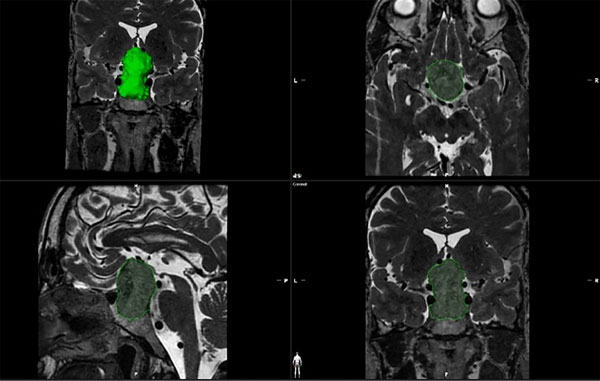

Se clasificaron las lesiones selares según el tamaño tumoral que presentaban en la RM prequirúrgica en la secuencia T1 con gadolinio y en la secuencia T2 FIESTA, ambas con más de 120 cortes. Se categorizó como “RM negativa” a la ausencia de lesión selar en el contexto de un paciente con una alteración analítica en el panel hormonal (asociado a otro estudio, como en el caso de un cateterismo de senos petrosos en la enfermedad de Cushing); el término “microadenoma” se designó para aquellas lesiones que presentaron un diámetro menor o igual a 10 mm en los 3 ejes (cefalocaudal, anteroposterior, y axial); “macroadenoma” para aquellas con un valor mayor a 10 mm en cualquier de los 3 ejes; y “adenoma gigante” para aquellas lesiones mayores a 4 cm en alguno de sus ejes.2 La variable “volumen tumoral” fue calculada por un mismo operador mediante la herramienta “smart brushing” del software de la compañía “BrainLab Elements”. Las áreas de interés correspondientes al tumor fueron manualmente delimitadas en las secuencias T1 volumétrico con gadolinio y T2 volumétrica de la RM prequirúrgica (Figura 2).

Figura 2. Método de obtención del volumen tumoral mediante la herramienta smart brushing. Este valor se obtiene al delimitar la lesión tumoral en sus tres ejes (axial, coronal y sagital).